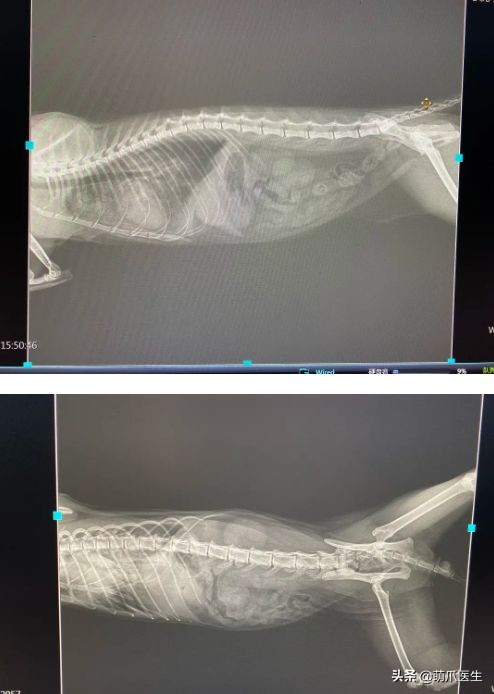

最后我们看一下X光片

go猫粮翻车了怎么处理,猫吃猫粮死了

腹腔未见明显异常,而胸腔里肺部有一些渗出心脏稍圆润偏大

前面说到,十一的生化检查结果显示有心肌损伤的可能性,并且X光片发现肺部有水肿或者渗出

而肺水肿会导致呼吸困难,每分钟呼吸次数超过50次。并出现严重的腹式呼吸